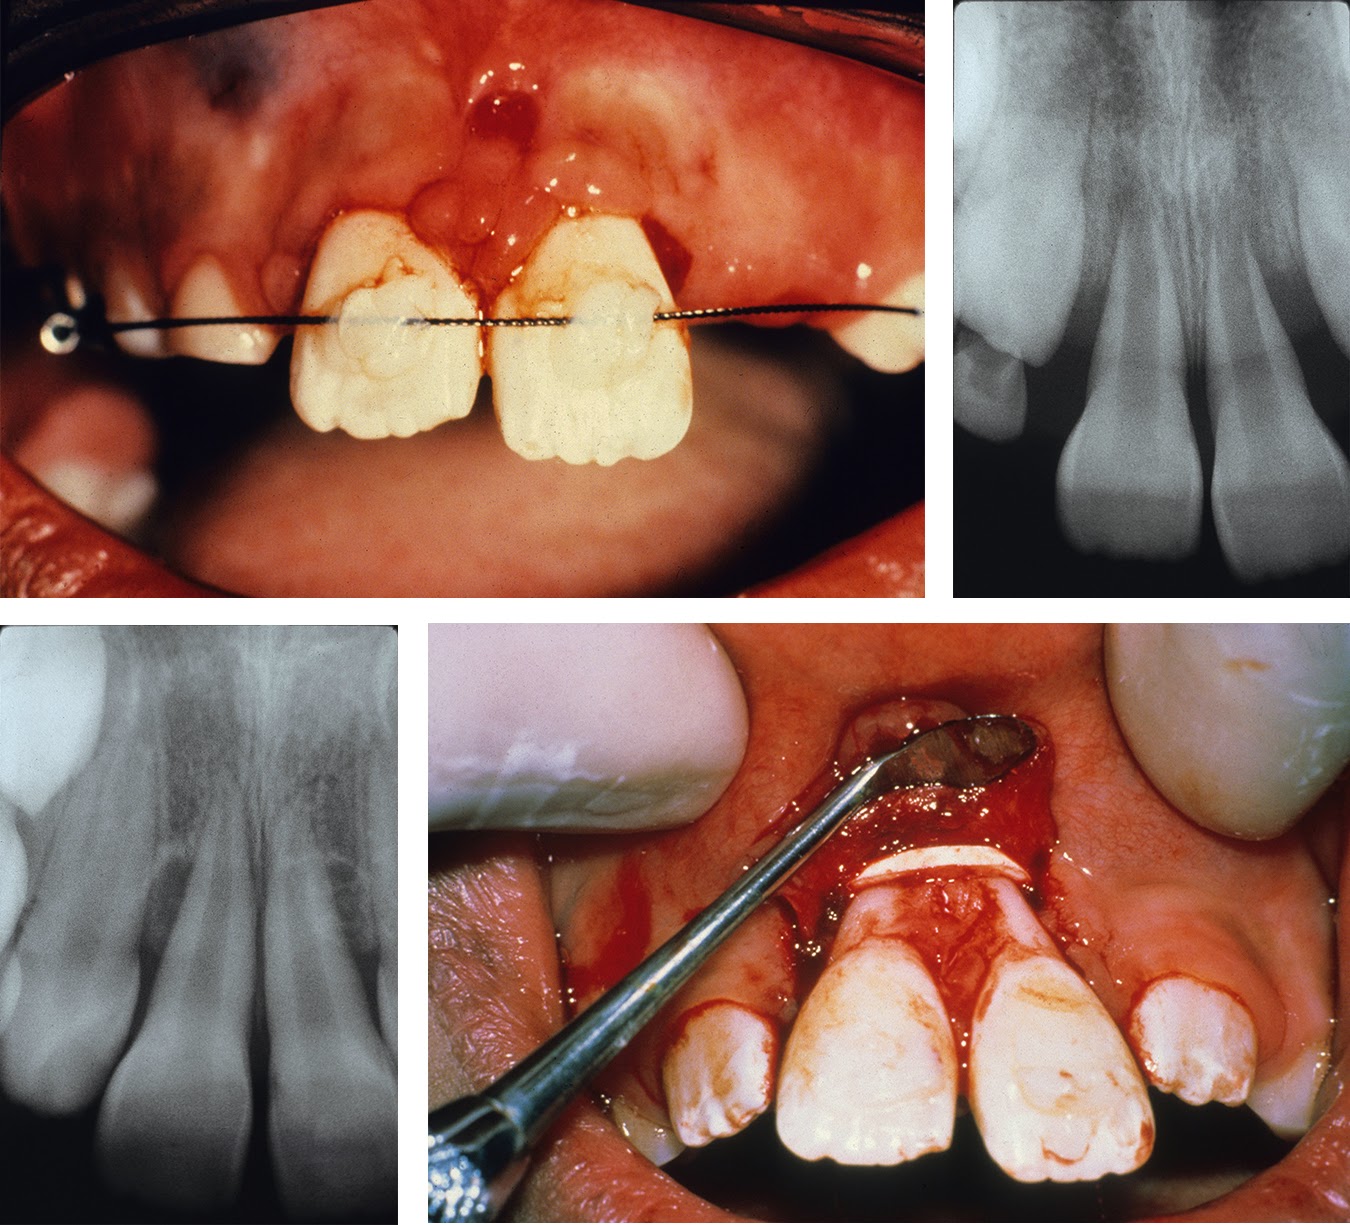

For example, people who have used “gap bands” they learned about on YouTube to close minor spaces between their teeth have caused irreparable damage to their teeth. While cheap cosmetic correction sounds appealing, the risk of losing your front two teeth just isn’t worth it. There are similar risks to be found in DIY braces and DIY clear aligners.